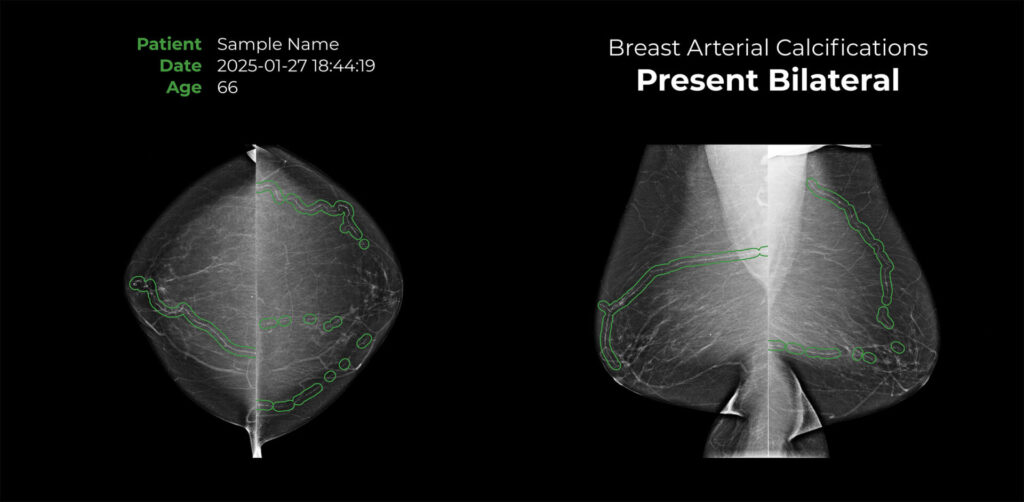

Mammo with Heart is an FDA-cleared, artificial intelligence (AI) based software intended to detect the presence or absence of breast arterial calcifications (BAC), an incidental finding in both Full Field Digital Mammogram (FFDM) and Digital Breast Tomosynthesis (DBT) screening mammograms.

The cmAngio software reads your mammograms to determine the presence or absence and location of breast arterial calcification. An expert radiologist will review your results to confirm the findings.